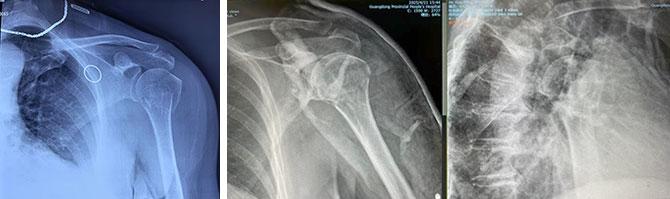

患者1:女,65岁,外科颈骨折

复位前 复位后